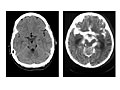

Exámenes de diagnóstico por imágenes. Un examen de imágenes por resonancia magnética (MRI, por sus siglas en inglés) o una tomografía computarizada (CT, por sus siglas en inglés), las cuales toman imágenes del interior del cuerpo, puede mostrar sangrado, hinchazón u otros cambios en el cerebro. Vea una imagen de un cerebro con encefalitis.